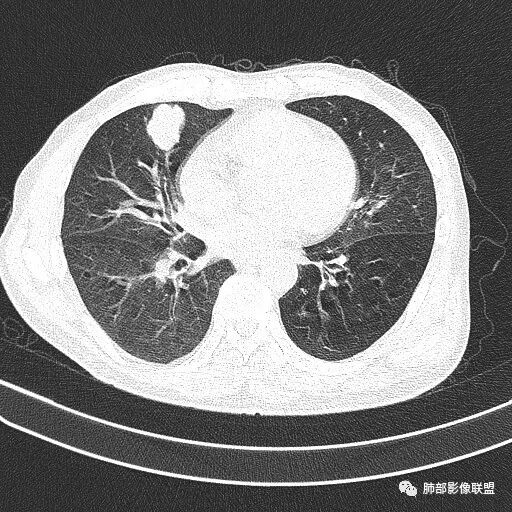

如果这时候我建议补充下面的层面,最好薄层

看起来堵了

南边:

按这个就是堵了

我们一般是找肺动脉,伴行支气管

堵了大方向不支持良性肿瘤

1.右肺中叶孤立不规则块影,浅分叶,未见液化或钙化,未见毛刺,未见脐凹,未见明显胸膜牵拉。

2.近肺门侧隐约见支气管截止。

3.外侧可见血管进入,病灶局部轻度强化。